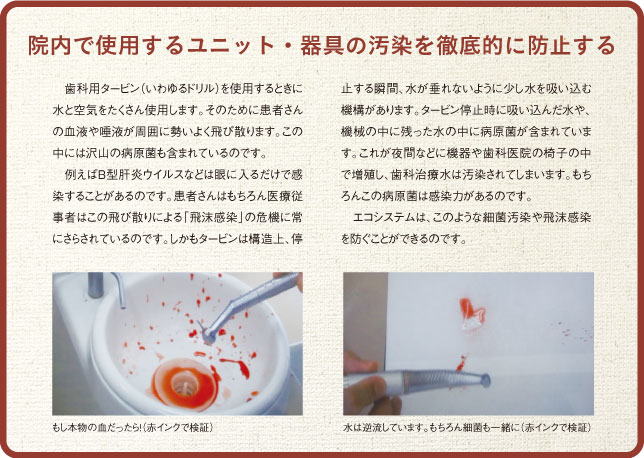

アーブル歯科クリニックは新型コロナウィルス第4波に対応できる様々な設備を整えています

新型コロナウィルスは飛沫感染します

治療時の飛沫により、患者様や医療従事者に飛沫感染する可能性があるため、治療時には口腔外バキュームを使用しています。

エピオスエコシステム

不純物を極限まで取り除いた「超純水」と純度99.9%の「塩」を混合し「電気分解」した薬品を全く使用しない、殺菌水です。虫歯菌・歯周病菌、一般的なウィルスを30秒程度で不活化することができます。

殺菌水なのに飲んでも習志野市で初めて導入された安全な医療用の治療水です。

アーブル歯科クリニックでは習志野市で初めて、エピオスエコシステムを導入し水道水ではなく、殺菌水で、虫歯治療や歯のクリーニングをしています。

毎年必ず、水質検査を行い、治療水が汚染していないか確認しています

水を出す大元から一番遠い歯科ユニットの水質検査をしても治療水から細菌は検出されませんでした

つまり、すべての歯科ユニットの治療水から細菌が検出されないということになります

歯科治療水安全認定施設賞証を6年連続で獲得。

飲んでも安全で清潔な治療水として認定されています。